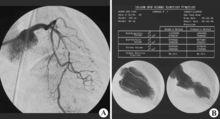

身體檢查 :心電圖 動態平板實驗 64排雙元CT 冠狀動脈造影

3、無症狀性心肌缺血型:很多病人有廣泛的冠狀動脈阻塞卻沒有感到過心絞痛,甚至有些病人在心肌梗塞時也沒感到心絞痛。部分病人在發生了心臟性猝死,常規體檢時發現心肌梗塞後才被發現.部分病人由於心電圖有缺血表現,發生了心律失常,或因為運動試驗陽性而做冠脈造影才發現。這類病人發生心臟性猝死和心肌梗塞的機會和有心絞痛的病人一樣,所以應注意平時的心臟保健。